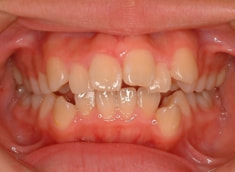

上顎前突ケース

治療法:表の矯正(T21ブラケット)

治療開始時

治療開始から5ヶ月後